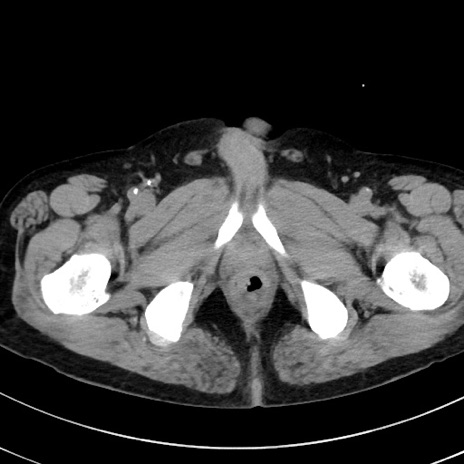

症例38(横断像)

【症例】70歳代 男性

【主訴】腹痛・嘔吐

【現病歴】昨晩より、嘔吐・腹痛あり。今朝になっても嘔吐あり。来院。

【既往歴】心臓バイパス手術、開腹胆摘、腸閉塞

【身体所見】BP 107/71mmHg、HR 116/min、腹部:平坦、軟、下腹部に軽度圧痛あり。反跳痛なし。

【データ】WBC 15100、CRP 0.32